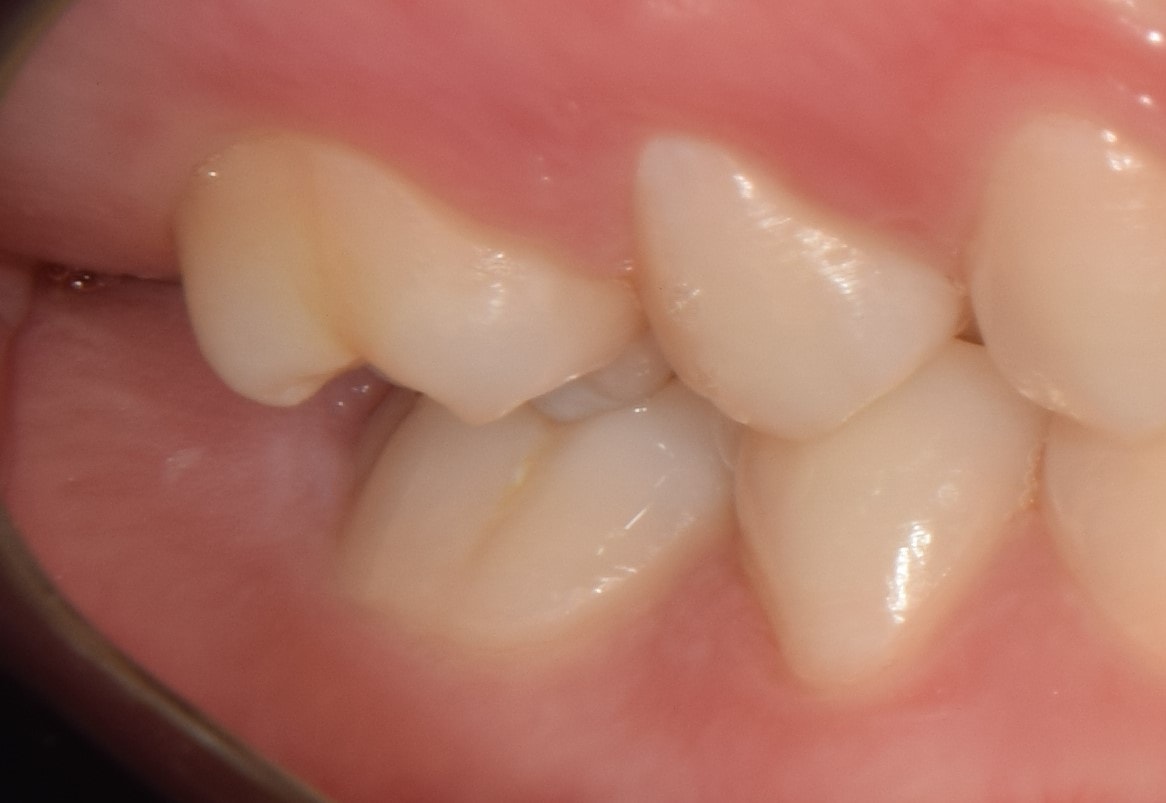

Impaktált fog

Impaktált fogaknak nevezzük azokat az előtörési hajlammal rendelkező fogakat, amelyek valamilyen akadály miatt az állcsontban ragadtak. Leggyakrabban a felső szemfogak és az alsó második nagyőrlők impaktálódnak, általában helyhiány miatt. Az impaktált fogakat fogszabályozó kezelés során sorba kell állítani, vagy el kell távolítani. Számos problémát okozhatnak, ciszta alakulhat ki körülöttük, károsíthatják a szomszédos fogakat vagy akár extrém helyzetben elő is törhetnek az idő előrehaladtával.